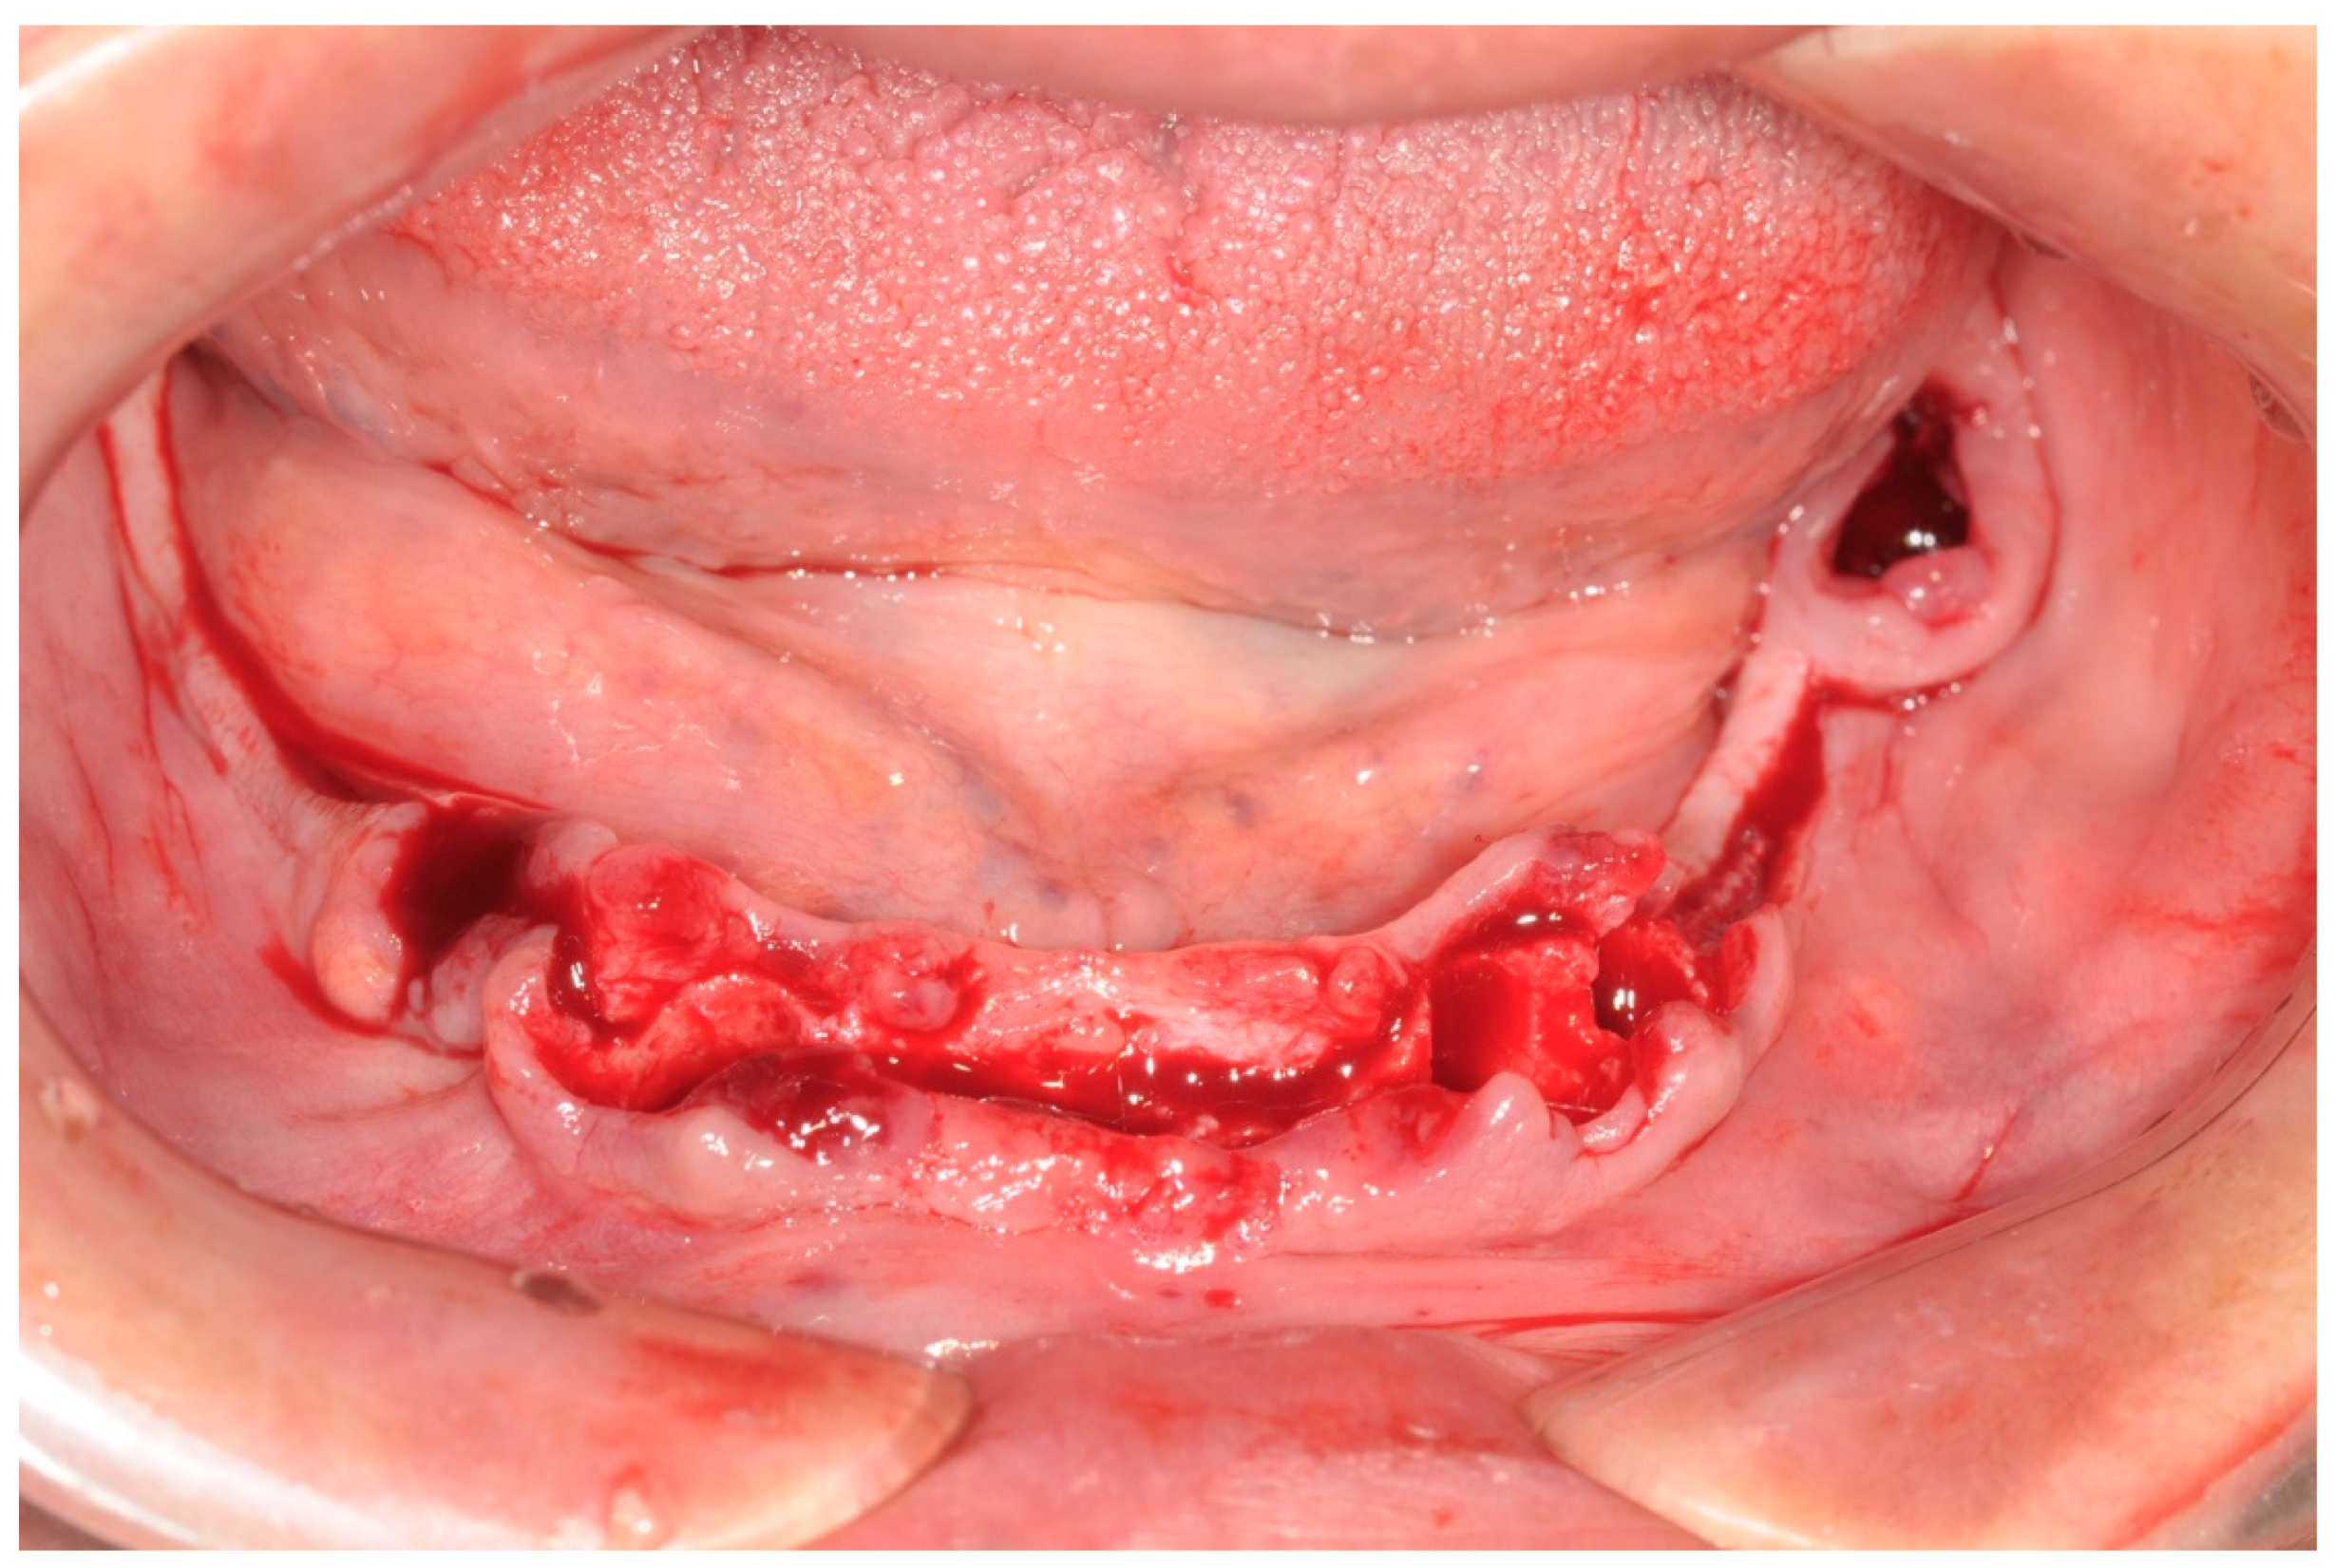

All patients were treated under local anesthesia, and patients received four, five, or six implants in the mandible according to the prosthetic treatment plan. In the case of tooth extraction sites, a periodontal probe was used to assess the integrity of the extraction socket’s bony walls and of the adjacent bone peaks to evaluate the feasibility of an immediate implant (Figure 2).

Figure 2. Operative site after tooth extractions.